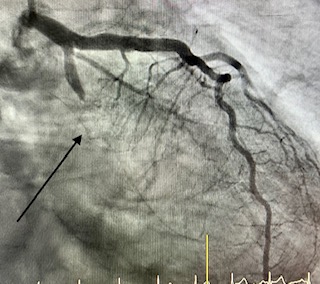

Angioplastia con stent

La angioplastia coronaria transluminal percutánea con implantación de stent ha sido capaz, en las salas de RX de los laboratorios de Hemodinámica y Cardiología Intervencionista, de combatir eficazmente a la enfermedad que más mortalidad causa en las sociedades modernas: la enfermedad coronaria.

Angioplastia con stent en un infarto (arteria cerrada 100%)